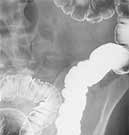

Tag: Colonoscopy